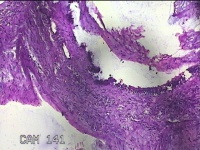

右侧卵巢囊肿

性别

女

年龄

36岁

临床诊断

一般病史

发现双侧附件囊肿1年。

标本名称

大体所见

灰白暗红色囊壁样组织2.5x2x0.3cm一块,表面光滑,部分已切开,囊内容物已流失,囊壁厚0.2cm。

考虑:子宫内膜异位囊肿。